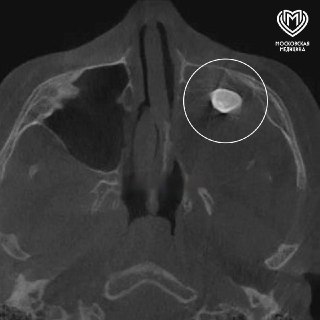

У 15-летнего москвича вырос в носу ЗУБ.

Сначала мальчик обратился к врачам с жалобами на асимметрию лица и заложенность носа. Уже в клинике специалисты обнаружили, что у подростка появился лишний зуб не на своем месте. К счастью, удалили его без проблем, юноша уже выписан с хорошим самочувствием.